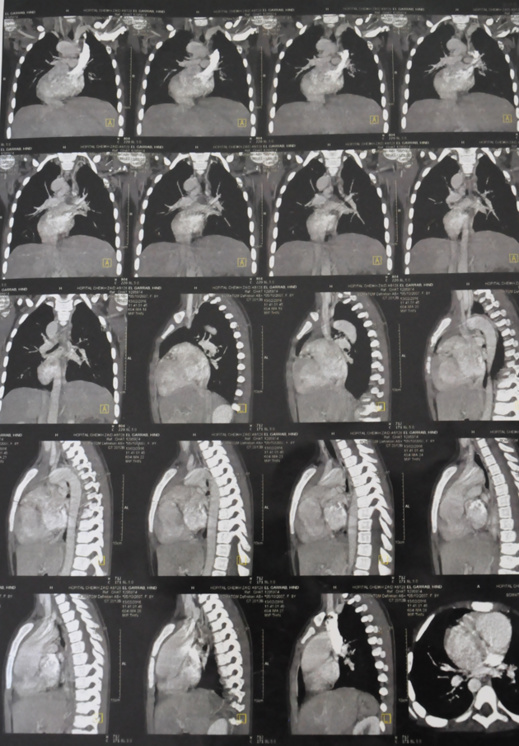

تعاني الطفلة "هند الكراب" البالغة من اللعمر 9 ربيعاً، والقاطنة برفقة أسرته بحيّ "زروالة" ببني أنصار، من مرض على مستوى القلب، وجراء ذلك أضحت تتعرض في حياتها اليومية لأزمات حادة في ضيق التنفس ونقص في الأكسجين والعياء وأعراض أخرى، ما يؤثر على حالتها الصحية ويهدد حياتها.

ولأجل تجاوز هذه الحالة المرضية تحتاج الطفلة "هند" إلى إجراء عملية جراحيـة مستعجلة على مستوى القلب، غير أنها مكلفة المصاريف، وبالموازاة مع ذلك فإن الحالة المادية لأسرة الطفلة المعنية بالعملية الجراحية، جد مزرية وضعيفة، وفي حاجة إلى يد المساعدة والتضامن من قبل المحسنين، لتمكينها من إجراء العملية بإحدى المستشفيات بالرباط.

وهذا نداء مستعجل إلى كل المحسنين الأفاضل وإلى كل من يرى في نفسه أريحية، وبإمكانه المساعدة لأجل ربط الاتصال عاجلا بوالدي الطفلة "هند الكراب" للاستفسار والمساعدة بقدر المستطاع، لأجل إنقاذ وتمكين الطفلة "هند" من إجراء العملية الجراحية اللازمة؛ والله لا يضيع أجر المحسنين، إذ يمكن الاتصال عبر الرقمين الهاتفيين التاليين الخاصين بأب وأم الطفة البرعومة هند:

0678123433 أو 0658127540